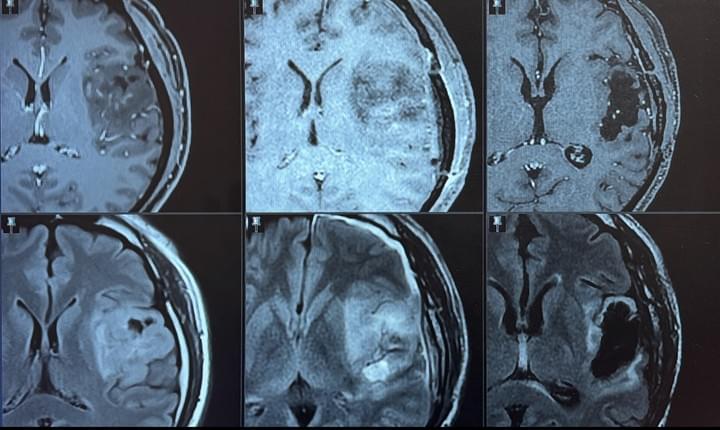

成人暨兒童神經外科雙專長 : 困難腦瘤、顱底手術與脊髓手術、功能性保護腦部手術、

高雄長庚莊銘榮醫師為南臺灣頗負盛名的神經外科醫師,很受病患信賴及圈內醫師推薦。他師承國內高雄長庚何治軍教授、北榮/北醫大黃棣棟教授、林長吳杰才主任、大里仁愛張國華教授(脊椎側彎)、林口長庚陳國鼎教授(顱顏矯正)、美國兒童神經外科大師Fredereck A. Boop教授(曼菲斯)、顱底手術大師Ali F. Krisht教授(小岩城)與腦膠質瘤手術大師Ugur Ture教授(伊斯坦堡)。他經過多年國內外大師親炙,專攻神經外科最困難的領域: 困難腦瘤、兒童、顱底、毛毛樣與癲癇手術。手術技術嚴謹精確,併發症甚低。他以神經功能保護與影像重建模擬聞名,擁有縝密的邏輯思考與臨床決斷,擅長複雜疾病的醫病溝通,重視人性價值與醫病共同決策。莊醫師在高雄長庚組建各領域成人與兒童神經外科疾病團隊,為中南台灣成人與兒童複雜的腦部脊髓疑難重症的後送轉介中心。

困難腦瘤與顱底手術

功能性保護的腦瘤手術

與全方位腦瘤團隊治療